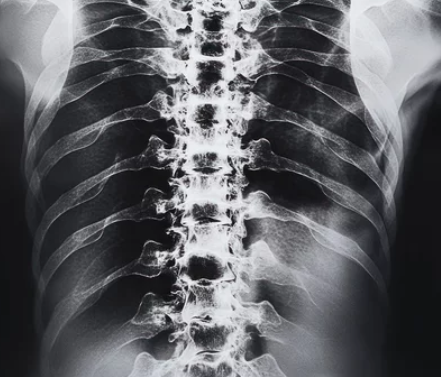

1. 척추 전방전위증이란?

척추 전방전위증은 하나의 척추 뼈가 다른 뼈보다 앞으로 밀려 나가면서 발생하는 척추 변형입니다. 이로 인해 신경을 자극하여 요통, 다리 저림 및 근력 저하 등의 증상을 초래할 수 있습니다. 주로 요추(허리)에서 발생하며, 노화, 외상, 유전적인 요인 등이 주요 원인으로 꼽힙니다.